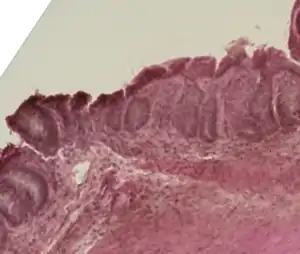

Mouse colon impacted by acute graft-versus-host disease.

In the clinical setting, graft-versus-host-disease is divided into acute and chronic forms, and scored or graded on the basis of the tissue affected and the severity of the reaction.[2][3]

In the classical sense, acute graft-versus-host-disease is characterized by selective damage to the liver, skin (rash), mucosa, and the gastrointestinal tract. Newer research indicates that other graft-versus-host-disease target organs include the immune system (the hematopoietic system, e.g., the bone marrow and the thymus) itself, and the lungs in the form of immune-mediated pneumonitis.[4] Biomarkers can be used to identify specific causes of GvHD, such as elafin in the skin.[5] Chronic graft-versus-host-disease also attacks the above organs, but over its long-term course can also cause damage to the connective tissue and exocrine glands.[6]

Acute GvHD of the GI tract can result in severe intestinal inflammation, sloughing of the mucosal membrane, severe diarrhea, abdominal pain, nausea, and vomiting.[11] This is typically diagnosed via intestinal biopsy. Liver GvHD is measured by the bilirubin level in acute patients.[12] Skin GvHD results in a diffuse red maculopapular rash,[13] sometimes in a lacy pattern.